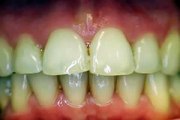

wsr ist die abkürzung für wurzelspitzenresektion. ein chirurgischer eingriff, der in der regel nichts bringt https://www.youtube.com/channel/UCtfezrProo8WbGBSwaEOMIA/search?query=wsr